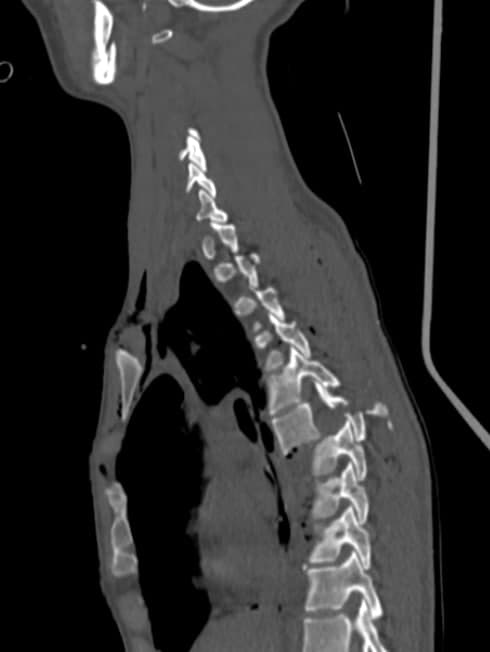

Как сообщил главврач областной больницы имени Мечникова Сергей Рыженко, их специалисты вместе с нейрохирургами из Харькова сделали операцию на позвоночнике девушке, у которой в результате аварии случился перелом семи позвонков в грудном отделе. По словам Сергея Рыженко, медики проводили процедуру так, чтоб после их вмешательства сохранились функции спинного мозга пациентки. Нужно сказать, что спинной мозг отвечает за многие жизненно важные автоматические процессы в организме человека, например дыхания и проглатывания пищи. Сергей Рыженко отмечает, что на утро после операции девушка могла двигать конечностями и улыбаться. Все прошло удачно и, вероятно, девушка не станет инвалидом.

Позвоночник пострадавшей в ДТП после операции/ фото: fb Сергея РыженкоПозвоночник пострадавшей в ДТП после операции/ фото: fb Сергея Рыженко